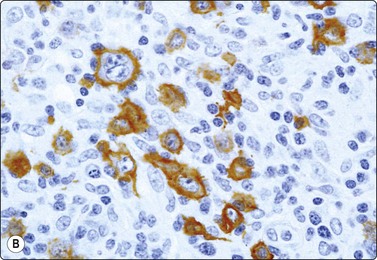

image image

Fig. 5.23 Merkel cell carcinoma

(A) FNB lymph node with predominantly dissociated undifferentiated tumor cells, superficially resembling NHL. However, lymphoid globules absent and lymphoid markers negative (MGG, HP). (B) Immunostaining of same case showing characteristic dot-like positivity of Merkel cell carcinoma with CAM 5.2 (HP).